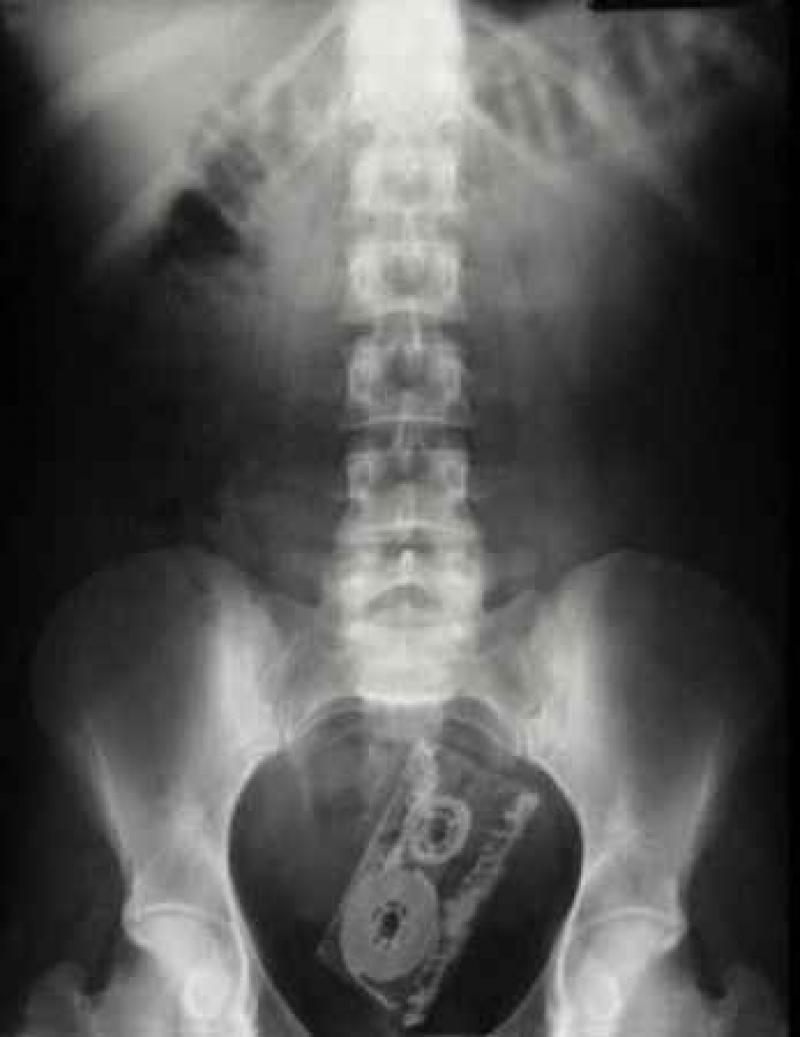

Röntgenfoto's zijn een medische uitvinding die ons al decennia lang helpt. Ze geven een nieuw gezichtspunt als het gaat om het vinden en behandelen van inwendige verwondingen. De machines kunnen opmerkelijke beelden vastleggen van het menselijk lichaam en ze documenteren vaak gruwelijke verwondingen. Een wonde van iemand zien, is al erg, maar als je ook kan zien wat de schade in het lichaam is, dat is nog veel erger. We hebben 12 tegelijk fascinerende, gruwelijke en hilarische röntgenfoto's op een rijtje gezet. Stel jezelf maar eens de vraag hoe iemand ooit aan die verwondingen is gekomen. We beginnen nog rustig.